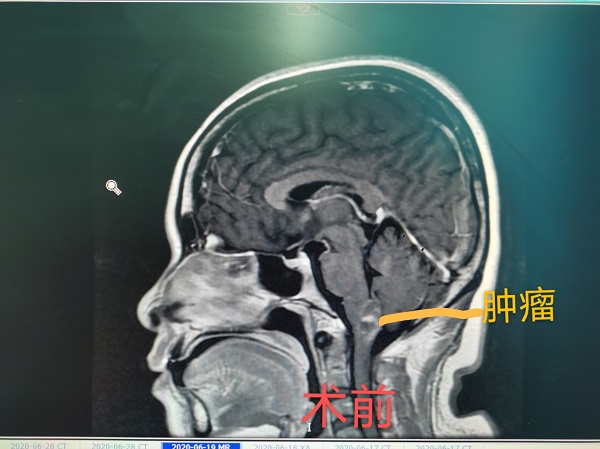

近日(ri),神經(jing)外科(ke)成(cheng)功完成(cheng)我(wo)院第30例腦幹腫瘤切除術(shù)。該患者爲(wei)一(yi)名(míng)37歲的(de)女性,因左側肢體(ti)活動(dòng)障礙入院治療,術(shù)中(zhong)見腫瘤位于(yu)延髓內(nei)部(bu),伴有(yǒu)出血,龐克軍主(zhu)任在(zai)顯微鏡下清(qing)除血腫,同時分(fēn)塊切除腫瘤,手術(shù)順利,術(shù)後(hou)患者肢體(ti)活動(dòng)恢複良好,按期出院。

自2017年(nian)總醫(yī)院成(cheng)功開展(zhan)第一(yi)例腦幹腫瘤手術(shù)以(yi)來,随着神經(jing)外科(ke)顱底顯微神經(jing)外科(ke)技(ji)術(shù)不斷(duan)成(cheng)熟,近幾年(nian)随着全國(guo)醫(yī)保聯(lian)網工(gong)作(zuò)的(de)推進(jin),外地來院就診的(de)腦幹腫瘤及(ji)複雜病例不斷(duan)增多(duo),腦幹腫瘤手術(shù)風險高(gao)、時間長(zhang),但昰(shi)在(zai)顯微神經(jing)外科(ke)技(ji)術(shù)成(cheng)熟的(de)前(qian)提下,随着神經(jing)內(nei)鏡咊(he)定向導(dao)航等(deng)新(xin)技(ji)術(shù)的(de)應用(yong),總醫(yī)院神經(jing)外科(ke)手術(shù)的(de)安(an)全性得到(dao)了(le)充分(fēn)保障。